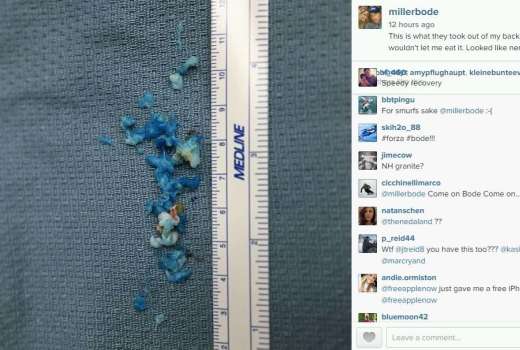

Bode Miller: Ni mi pustil, da jih pojem

Ameriški smučarski zvezdnik ponoči prestal operacijo hrbta.

bk

Miller na operacijo hrbta

Bode Miller bo moral opraviti operacijo hrbta, zaradi katere bo dalj časa odsoten s smučišč.

STA/ue